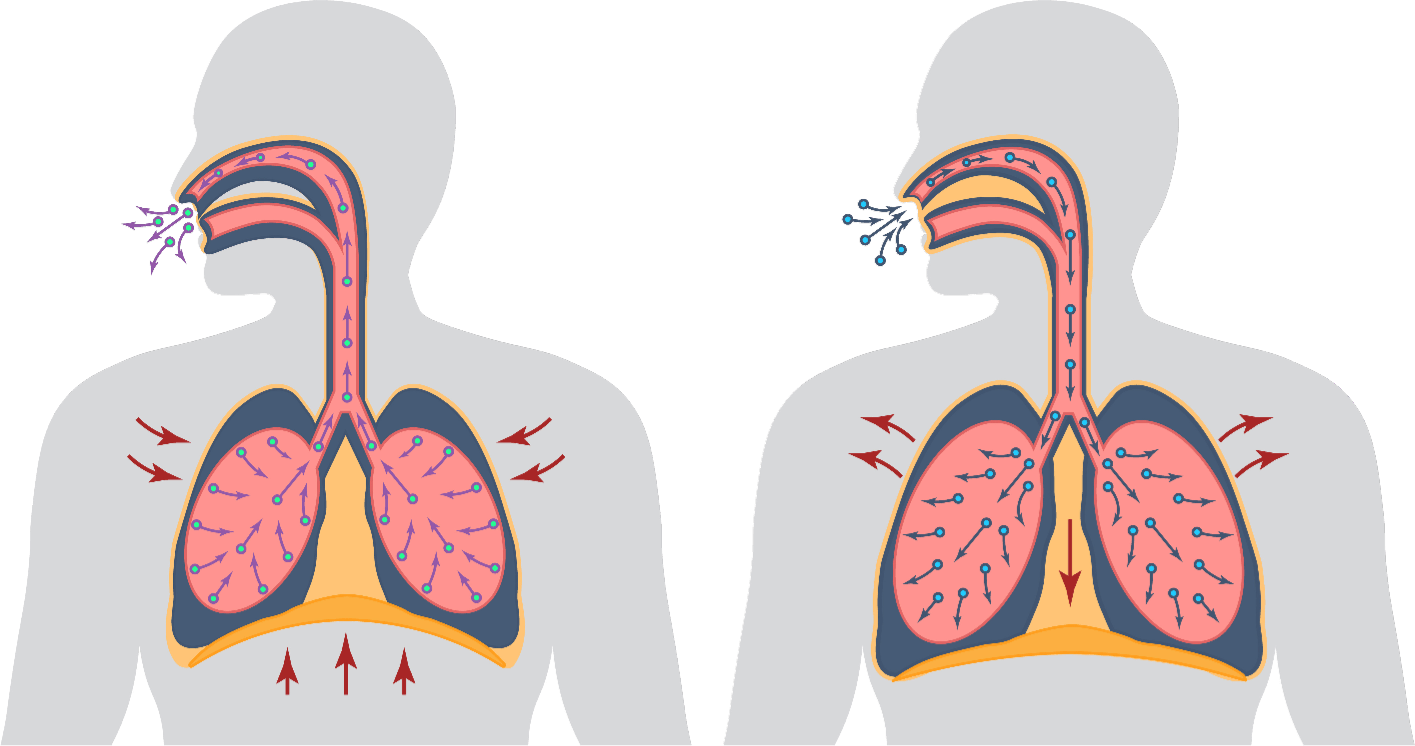

MECHANISM OF ACTIONS (MOA)

EA 575® is also unique to help improve respiratory function in patients with bronchitis.

- The EA 575® is an active ingredient from natural ivy leaf which liquefies the sticky mucus trapped in the air passages of the lungs.

- It then acts as an expectorant, allowing the mucus to be coughed up more easily.

- As the air passages relax and widen, you are able to breathe better and more comfortably.